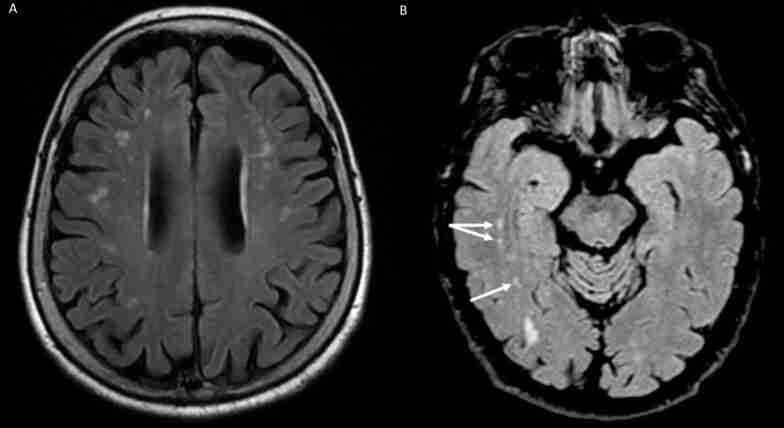

Recent research has identified an elevated incidence of White Matter Hyperintensities (WMHs) in specific brain regions of BMS patients, particularly in the frontal, parieto-occipital, and temporal areas. These WMHs, visible on MRI through T2-weighted or Fluid Attenuated Inversion Recovery (FLAIR) sequences, are early indicators of brain vulnerability and may signify accelerated brain aging (Fig. 3).

They are associated with cerebral small vessel arteriolosclerosis and potential links to vascular dementia and neurodegenerative diseases like Alzheimer’s. The connection between chronic orofacial pain, including BMS, and WMHs remains debated, with uncertainty about whether WMHs contribute to the onset of chronic pain or exacerbate BMS symptoms [ref. 36]. A recent study by Kato et al. [ref. 23] used Diffusion Tensor Imaging (DTI) and Neurite Orientation Dispersion and Density Imaging (NODDI) to evaluate white and gray matter abnormality in BMS. The study included 14 BMS patients and 11 healthy controls, analyzing various metrics such as fractional anisotropy (FA), mean diffusivity (MD), axial diffusivity (AD), radial diffusivity (RD), intracellular volume fraction (ICVF), and isotropic volume fraction (ISO). Results showed that BMS patients exhibited higher FA and ICVF and lower MD and RD in widespread white matter areas, as well as higher ISO and lower MD and RD predominantly in the amygdala. These findings suggest microstructural changes in both white and grey matter, indicating alterations in myelination, astrocytic hypertrophy, and neuroinflammation, reflecting the complex pathology of BMS [ref. 23].